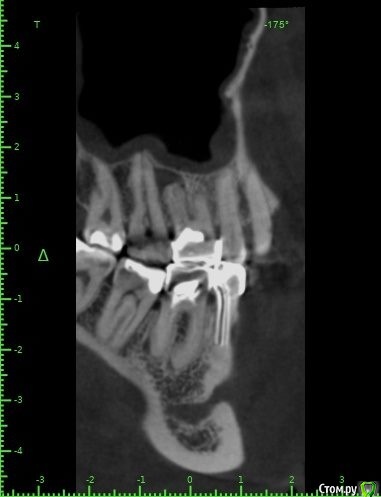

Raystom Опубликовано 20 февраля, 2021 Поделиться Опубликовано 20 февраля, 2021 Обратилась пациентка с неприятными ощущениями в области зубов 26, 27, во рту эти зубы показались мне темнее остальных, на КТ видна вот такая красота. Каков план лечения в таких ситуациях? Попробовать отделить пазуху от грануляций или просто удалить и после лечения ЛОРа идти на закрытие ОАС? Как после восстанавливать кость? И какие временные промежутки. Понимаю, что многие скажут при таких вопросах передать другим, но это не мой вариант. Мб есть литература по подобным случаям? Ссылка на комментарий

It'sGeorgy Опубликовано 20 февраля, 2021 Поделиться Опубликовано 20 февраля, 2021 А что именно смущает? Что дефект с пазухой сообщается? Так закроете после удаления, ничего страшного. ЛОРу, имхо, там делать нечего пока еще.Недавно был подобный случай: А вообще, судя по тем скринам, которые вы выложили, я бы пациента терапевтам показал для начала. Ссылка на комментарий

Raystom Опубликовано 20 февраля, 2021 Автор Поделиться Опубликовано 20 февраля, 2021 А что именно смущает? Что дефект с пазухой сообщается? Так закроете после удаления, ничего страшного. ЛОРу, имхо, там делать нечего пока еще.Недавно был подобный случай:12.png23.png22.png А вообще, судя по тем скринам, которые вы выложили, я бы пациента терапевтам показал для начала.Именно, что с пазухой. С терапевтами общались, при попытке препарирования зуб "мягкий", как кариозный судя по их словам Ссылка на комментарий

Карен Аванесов Опубликовано 22 февраля, 2021 Поделиться Опубликовано 22 февраля, 2021 Обратилась пациентка с неприятными ощущениями в области зубов 26, 27, во рту эти зубы показались мне темнее остальных, на КТ видна вот такая красота. Каков план лечения в таких ситуациях? Попробовать отделить пазуху от грануляций или просто удалить и после лечения ЛОРа идти на закрытие ОАС? Как после восстанавливать кость? И какие временные промежутки. Понимаю, что многие скажут при таких вопросах передать другим, но это не мой вариант. Мб есть литература по подобным случаям?Аккуратно удалить, убрать грануляции, инструментально уточнить есть ли сообщение с пазухой (Думаю что нет), если и есть, коллаген, и лунку ушит. Динамичный контроль. Ссылка на комментарий